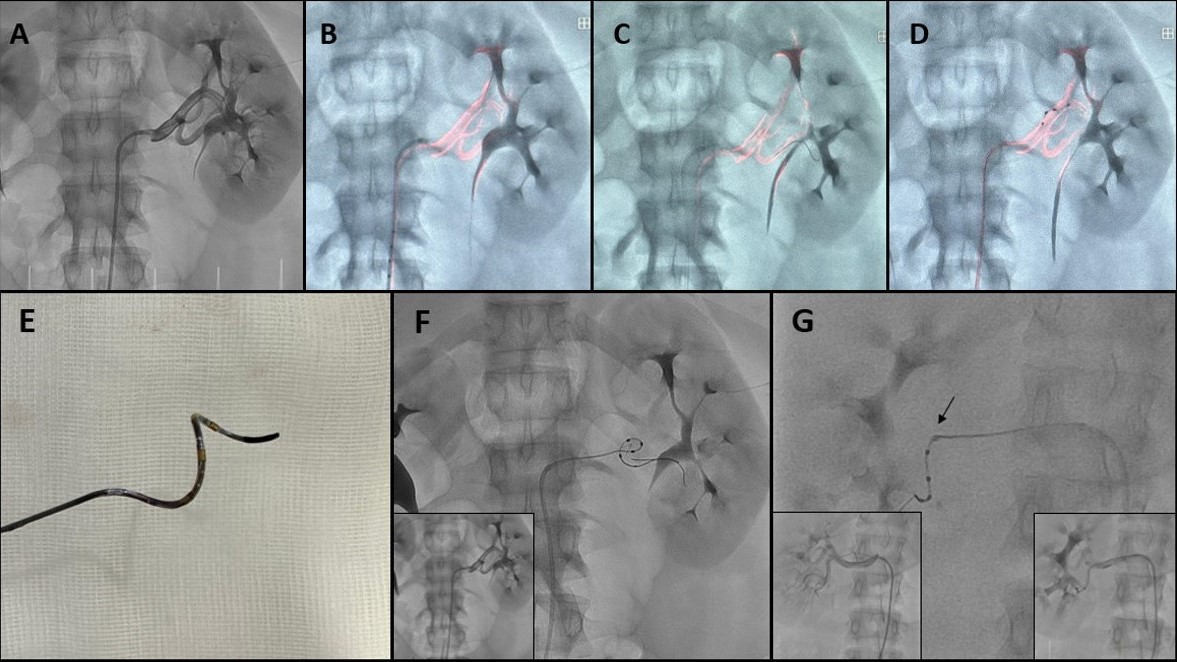

RDN is a minimally invasive procedure that involves a catheter-based ablation of the sympathetic nerves within the renal artery. DRM projects a highlighted renal angiogram superimposed on a live 2-dimensional fluoroscopic image, creating a colored roadmap (Figure, A & B) that adjusts automatically with a single 5-mL injection of contrast medium. It also provides continuous visual feedback on the positioning of the wire (Figure, C) and the catheter (Figure, D). The use of this coronary tool allows for the reduction of both radiation doses and contrast volume, providing improved safety for patients with resistant hypertension, especially for those at higher risk of contrast-induced nephropathy.

RDN is a technically simple procedure, however, the advancement of the Symplicity-Spyral catheter (SCC) (Medtronic) (Figure, E) can sometimes be challenging due to its helical shape and stiffness, mainly in angulated or tortuous branches. In these cases, coronary techniques such as buddy wire (Figure, F) or the use of guide catheter extension (Figure, G [arrow]) can improve the guiding catheter stability and support, and facilitate SCC navigation to the radiofrequency application site.